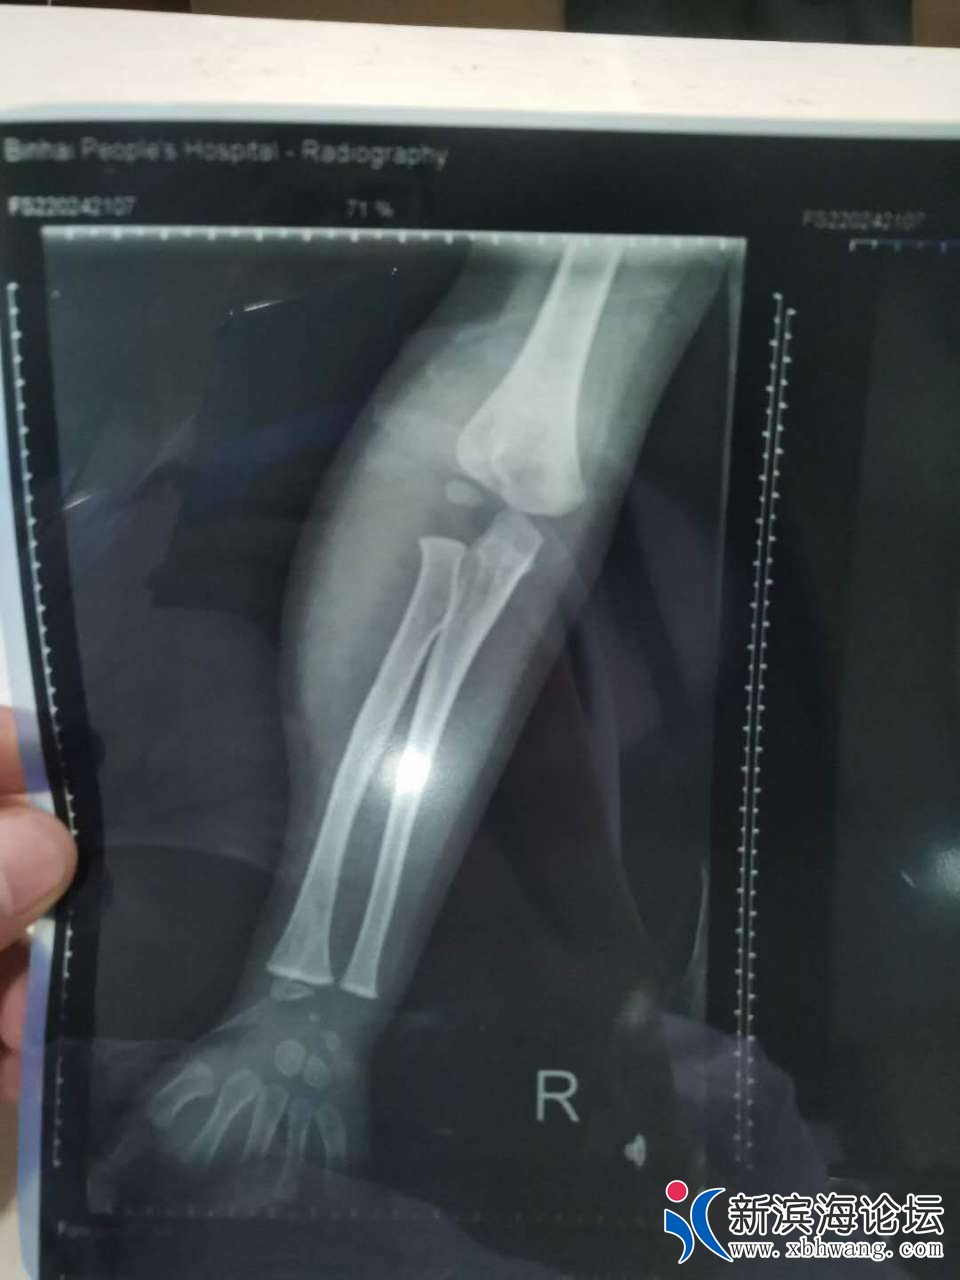

大家好 我是孩子的爸爸   3.31号晚  宝宝不小心从床上摔下来  家人比较担心  就带宝宝来到滨海第一人民医院就诊  挂完号我们等了很久才等到医生过来  简单两句话   就让我们去做血常规  再拍个片子  还嘱咐我们拍完 不用等片子出来   他可以从电脑上看  我们也不懂  就听了医生的话   等医生从电脑上看完片子  告诉我们说宝宝没有什么事  就是有点血肿  让我们回去冰敷一下就可以了  宝宝比较坚强  也没有哭  我们就相信了医生的话  带宝宝回家了  可是再到4.30号总觉得宝宝胳膊使不上力气  再次带着宝宝来到县医院复查  等来的结果却是骨折了  而且还要动手术  我们质疑了  因为3.31号晚上的片子  县医院有3个医生看过  都说没有问题   于是带着之前的片子和5月1号的片子来到其他几个医院   结果给我们的诊断都很肯定宝宝的胳膊骨折了   看过3月31号的片子  也都说  之前的片子就看的出来是骨折了  现在要动手术  而且还担心留下残疾    瞬间就感觉天塌下来了  很相信我们滨海的县级医院   结果给宝宝误诊了   现在已经一个月下来了     宝宝耽误了最佳治疗时期   滨海其他医院已经不接收这么小的宝宝 因为也错过了最佳治疗时间  我们再次来到县医院  想处理下宝宝现在的状况  可是 医院找各种理由  推脱      找到当日的值班医生  现在还不承认  说他没错  还让我们去骨科再看   真就不明白  来到医院  挂号  如果你看不了这个病  为什么让我们去做一系列的检查  还给我们诊断结果  说只是血肿  未见骨折现象     院方一味的找借口推脱  一副天不怕地不怕的样子  你们的良心不会痛吗   你们自己家里没有宝宝吗 以前总是在别人嘴里说县医院太差劲 这次,我们也算是真见到了  庸医  真的是害惨了我们一家人  特别是宝宝  他还4周岁不到  这么小  就遭这么大的罪   还有可能留下残疾的症状     真的就是黑心医院无良医生   也请有关上级领导帮忙彻查此次医疗事故  感谢不尽   下面附上宝宝两次拍的片子  前3张是3.31号晚上的   最后两张是5.1号的

你好,首先感谢你对我院工作的关心和支持,关于你反映的“县医院医生···”一事,我院高度重视,立即组织相关科室调查具体情况,患儿崔某某,男,4岁,因”意外伤"于2020年03月31日晚来我院急诊外科就诊,摄片见肱骨髁旁高密度影,考虑骨骺(小儿肘关节骨骺易与骨折混淆),初诊时不能明确,建议患儿家长三天后至我院骨科门诊复诊,患儿家长因为孩子肿痛不明显,未及时来院诊治,一个月后复查提示肱骨外科骨折,事情发生后,我院已经安排专人对接,目前正与患儿家长商讨下一步诊疗方案。最后再次感谢你对我院工作的关心和监督。